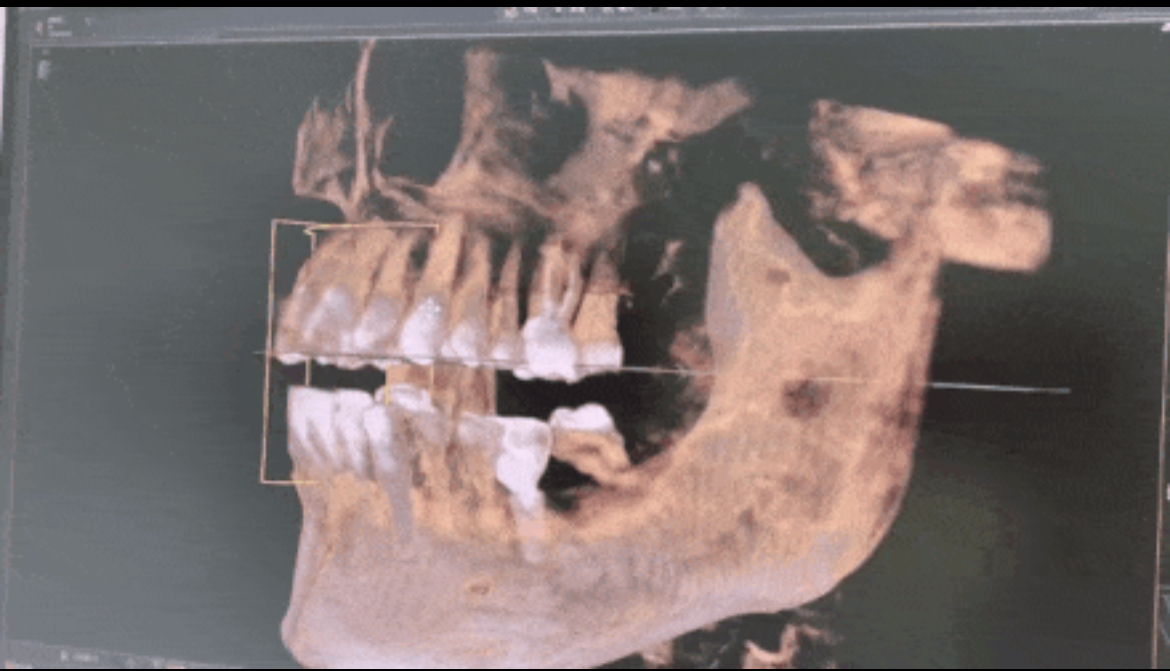

在海德堡联合口腔植入骨粉前会根据Sirona CBCT全景影像片设备得出的数据严格分析牙槽骨骨量的密度、高度等,做到精确,再精确!

■首先患者只需要通过CBCT进行全面扫描,可以显示出三维口腔结构,再通过3shape口扫对患者的口腔信息进行数字化采集。包括患者牙槽骨厚薄、高低,甚至血管神经的精确位置。

▲CBCT可以得到三维图像,更加直观精准

再根据方案用临时树脂牙模上标记好的放射点,进行第二次图像拍摄。

将两次图像进行拟合比对,很快就能找到适合种植的牙槽骨位置和种植位点。